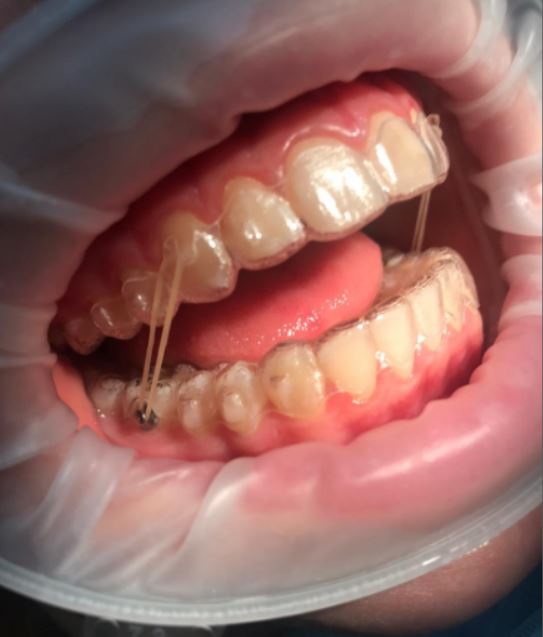

שימוש בכפתורים וגומיות בין לסתיות

לעיתים במהלך הטיפול ישנו צורך בסגירת מנשך פתוח שנובע מעמדה לקויה של הלסתות ו/או השיניים ואינו מאפשר מגע בין השיניים העליונות לשיניים התחתונות, לצורך זה יש לעיתים להרכיב גומיות בין לסתיות שלרוב מעוגנות בכפתורים מהסוג המודגם בתמונות.

גומיות בין לסתיות

לקראת סוף הטיפול בחלק מהמקרים יהיה צורך בגומיות שהמטופל מרכיב מלסת אחת לשניה. הן קלות להרכבה עצמית, ומאפשרות לרופא לסיים את ישור השיניים עם סגר תקין וסידור שיניים נכון. את הגומיות יש להרכיב לפי הוראות הרופא למרבית שעות היום.